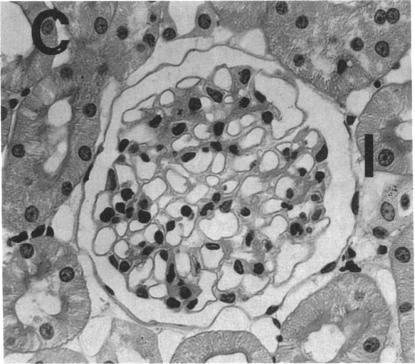

Reactive oxygen species, particularly hydrogen peroxide (H2O2), participate in neutrophil-mediated glomerulonephritis. However, the mechanism of H2O2 neptrotoxicity is unknown. Myeloperoxidase (MPO), a neutrophil cationic enzyme that localizes in glomeruli, can react with H2O2 and halides to form highly reactive products. We tested the hypothesis that the MPO-H2O2-halide system may induce glomerular injury by infusing MPO followed by H2O2 in a chloride-containing solution into the renal artery of rats. Controls received MPO or H2O2 alone. MPO-H2O2-perfused rats developed significant proteinuria, endothelial cell swelling, and epithelial cell foot process effacement, whereas control kidneys were normal. In the presence of free 125I, MPO-H2O2-perfused rats incorporated large amounts of 125I, localized to the glomerular basement membrane and mesangium by autoradiography, into glomeruli. Glomerular iodination was greatly decreased or absent in controls. The MPO-H2O2-halide system causes glomerular injury and may be important in neutrophil-mediated glomerulonephritis.

活性氧物质,尤其是过氧化氢(H2O2),参与中性粒细胞介导的肾小球肾炎。然而,H2O2肾毒性的机制尚不清楚。髓过氧化物酶(MPO)是一种定位于肾小球的中性粒细胞阳离子酶,可与H2O2和卤化物反应形成高活性产物。我们通过将MPO然后在含氯溶液中的H2O2注入大鼠肾动脉,来检验MPO-H2O2-卤化物系统可能诱导肾小球损伤的假说。对照组单独接受MPO或H2O2。接受MPO-H2O2灌注的大鼠出现显著蛋白尿、内皮细胞肿胀和上皮细胞足突消失,而对照肾脏正常。在游离125I存在的情况下,接受MPO-H2O2灌注的大鼠肾小球大量摄取125I,通过放射自显影定位到肾小球基底膜和系膜。对照组肾小球碘化作用大大降低或不存在。MPO-H2O2-卤化物系统导致肾小球损伤,可能在中性粒细胞介导的肾小球肾炎中起重要作用。